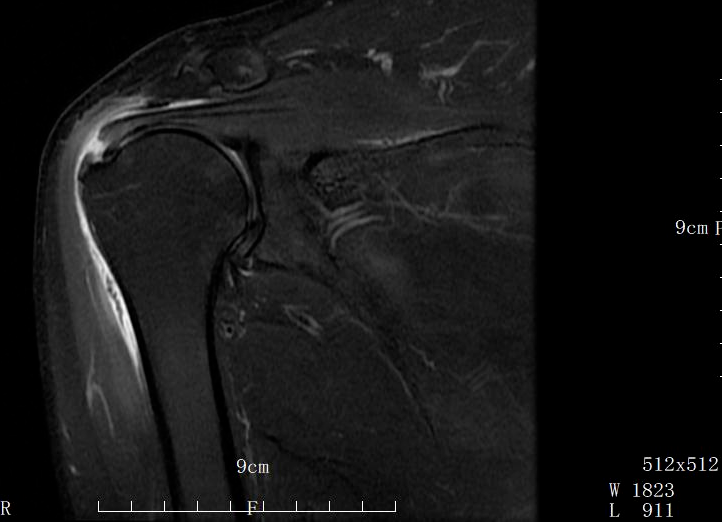

骨科周武忠主任讲到了这样一位患者,40多岁的李女士(化名)摔了一跤,肩膀着地,陆陆续续的疼痛,疼的就贴点膏药,也接受过针灸、拔罐这些中医理疗,在家附近医院诊断为肩周炎,吃药、药敷、护具,可是半年多过去了,肩部酸痛缓解了,但手臂却越来越没力,抬不起来,自己梳头都不行,更别说一些稍微用点体力的活动。8月底,来到我院检查,周武忠主任发现她情况比较严重,肩袖断口明显,是非常明显的肩袖撕裂病症,而非肩周炎。

肩周炎也以肩关节疼痛和活动受限为主要症状,约占肩关节疼痛20%。肩周炎是因关节软组织退变及受风寒引起的关节囊和关节周围软组织的慢性无菌性炎症,炎症导致关节内外粘连,从而影响肩关节活动。大多数肩关节炎经适当锻炼和养护可自愈,通过核磁检查可以鉴别两种疾病。

根据李女士的具体病情,周武忠主任团队为她行关节镜下肩袖修补术,通过小切口置入关节镜,镜下精准缝合,将撕裂的肩袖肌腱重新固定于肱骨大结节,恢复肩关节稳定性,术后,李女士感觉疼痛明显减轻。